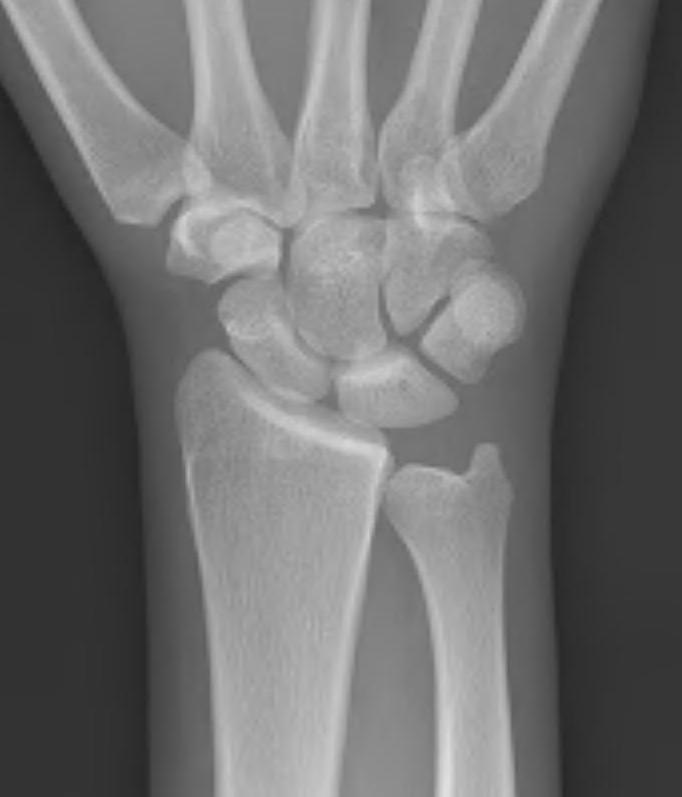

Xray

Progressive changes of AVN

- sclerosis

- fragmentation / fracture / flattenging

- midcarpal collapse: scaphoid flexion / capitate descent

- radiocarpal and midcarpal osteoarthritis

Lichtmann Classification

Stage I

- xray normal

| Stage II | Stage IIIA |

| Sclerosis |

Collapse / fragmentation Normal carpal height |